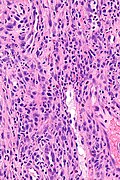

TUGSE. H&E stain. (WC/Nephron) | |

| LM | stromal eosinophils and lymphocytes, ulceration. |

Features:[2]

- Stromal eosinophils and lymphocytes.

- Ulceration.